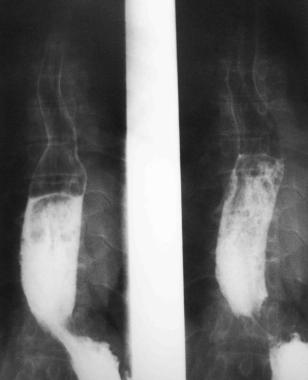

Поражение толстой кишкиприводит к запорам (менее 2 спонтанных дефекаций в неделю) и недержанию кала; встречается с такой же частотой, как и гипотония пищевода («стеклянный пищевод») (рис.5-5).

Рис. 5-5. «Стеклянный пищевод».